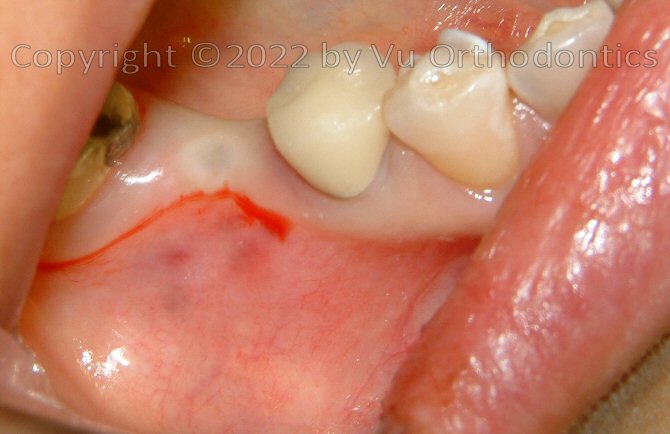

Fig. 11. After the implant was buried (w/ a cap screw), ready for Free Gingival Graft (FGG), poor keratinized mucosa was apparent

Fig. 12. FGG was performed

Fig. 13. The donor site on the palate, for the FGG

Fig. 14. At the end, good keratinized mucosa is apparent (good seal/protection for the implant, after FGG)